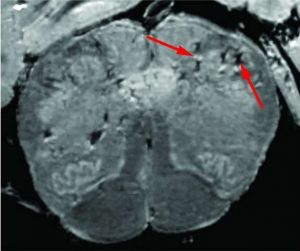

Brain damage of patients with Covid-19 In an in-depth study of how COVID-19 affects a patient’s brain, National Institutes of